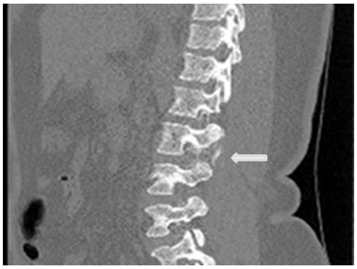

Under the suspicion of intracranial hypotensive headache caused by acute CSF leakage, a CT myelogram was performed Figure 3 the needle was set at L3/4 under radiographic control, contrast was repeatedly injected and x-ray images of lower and upper spine performed. After filling up to the cervical level of the epidural space, the patient’s whole spine was imaged with CT and extravasation was noted Figures 4 & 5.

Figure 5 white arrows pointing to contrast extravasation.